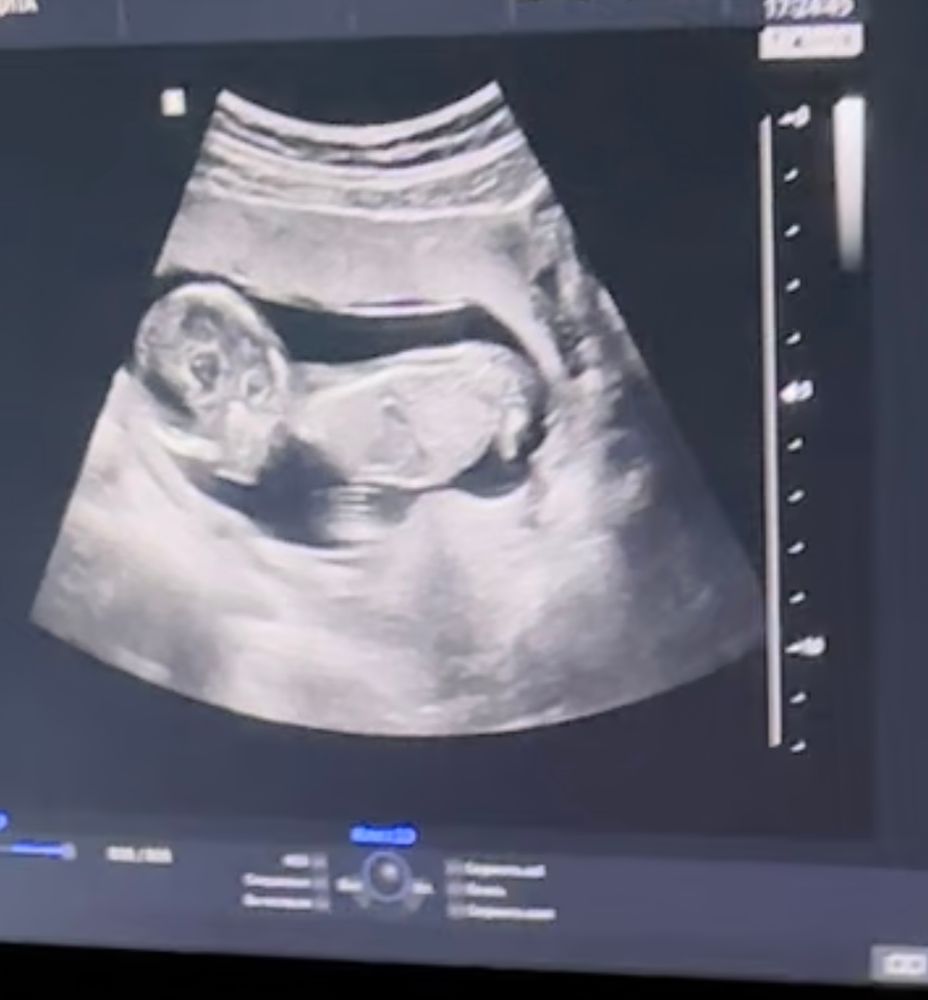

Это половой бугорок? Кто разбирается?

Ой да не поймешь так, могли ноги так на узи отражаться. Так в сказали вам пол в итоге? Если бугорок, то я сказала бы мальчик.

Victoria, ну она долго так рассматривала, муж снимал видео узи. Это я заметила на первой минуте. Просто после этого еще долго смотрела. Потом сказала мальчик

Диана, ну обычно на этом сроке уже точно видно. Мальчика как мне говорил узист в целом видно с 12 недель, а вот девочка в 12 недель еще может стать мальчиком чуть позже:) думаю точно мальчик

Если это половой бугорок, то 100% мальчик

Вера, надеюсь, что ножки🤭